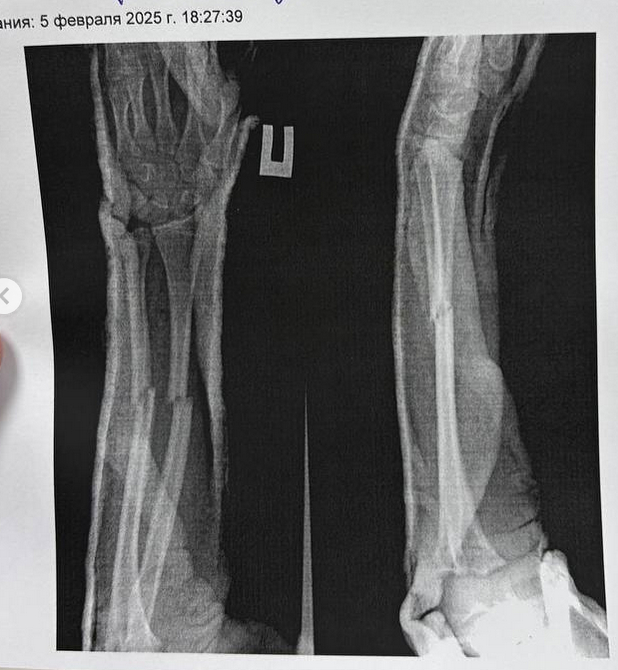

В начале февраля 2025 года в школе № 6 города Нижнекамска 12-летний шестиклассник (из семьи узбекского происхождения, но с российским гражданством) решил продемонстрировать однокласснице прием из борьбы: он перекинул девочку через плечо и бросил на пол. В результате у девочки произошел перелом костей обеих рук. Девочку срочно прооперировали под общим наркозом, впереди у неё длительная реабилитация (врачи отмечали, что кости срастаются непросто, и впереди у ребенка долгая физиотерапия и восстановление функций рук)